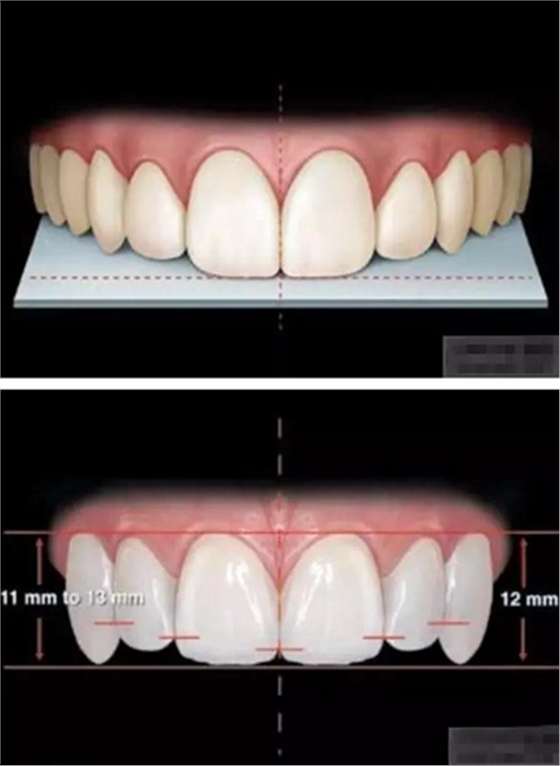

審美序列清單:

1、切牙的位置長度

2.頜學(xué)

3.牙齒寬度

前牙的黃金分割比例

正面觀

側(cè)切牙約為中切牙的60%

尖牙約為側(cè)切牙的60%

4.牙齒比例

中切牙正常/理想的 寬/長百分比約為75%—80%